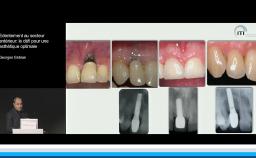

Après avoir fait une revue exhaustive de la littérature sur les principes biologiques conduisant à la résorption des tables osseuses alvéolaires après une extraction, Mark Bischof aborde l’historique des techniques qui ont été proposées depuis 20 ans pour préserver l’intégrité et l’apparence des tissus osseux et muqueux dans le cadre de réhabilitations prothétiques implant-portées. Reposant sur la littérature, il nous propose une lecture critique et argumentée des différentes options qui seront illustrées de cas cliniques démonstratifs.

Des critères objectifs d’évaluation sont proposés pour appréhender l’impact tissulaire d’une extraction.